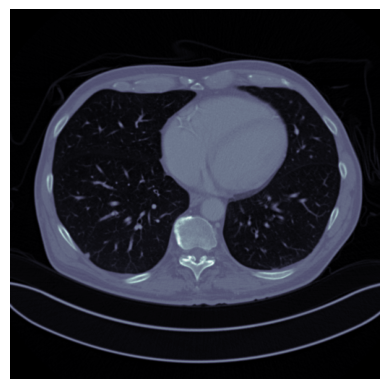

In this section, we consider a sparse-view computed tomography (CT) reconstruction task, with human abdominal CT scans of the Mayo clinic for the low-dose CT grand challenge [44] as training and testing data. The measurements are simulated using a parallel beam geometry with 200 angles and 400 bins. We model the noise as Poisson with a constant background level r=50r=50, that is 𝐲Pois(𝐀𝐱+r)\mathbf{y}\sim\text{Pois}(\mathbf{Ax}+r), where 𝐀\mathbf{A} is the scaled X-ray transform with the prescribed geometry. We take 2240 slices with batch size 20 from 9 patients as training ground truth data, and the filtered back projections (FBP) are used as degraded samples for training. The regularizer is trained for 20 epochs with a learning rate of of 2e2e-55, (β1,β2)=(0.5,0.99)(\beta_{1},\beta_{2})=(0.5,0.99), batch size of 20, and λGP=30\lambda_{GP}=30. For reconstruction, we consider the Kullback–Leibler (KL) divergence data fidelity, which is suitable for Poisson-distributed data:

Refer to caption

Ground Truth

Refer to caption31.06

Proposed, 50 iter

Refer to caption26.19

SM-C, 50 iter

Refer to caption26.67

SM-D, 50 iter

Refer to caption21.29

FBP

Refer to caption31.16

Proposed, 500 iter

SM-C, 500 iter

Refer to caption29.06

SM-D, 500 iter

Figure 7: CT: Visual comparison of reconstructions, with PSNR shown at top right corner.